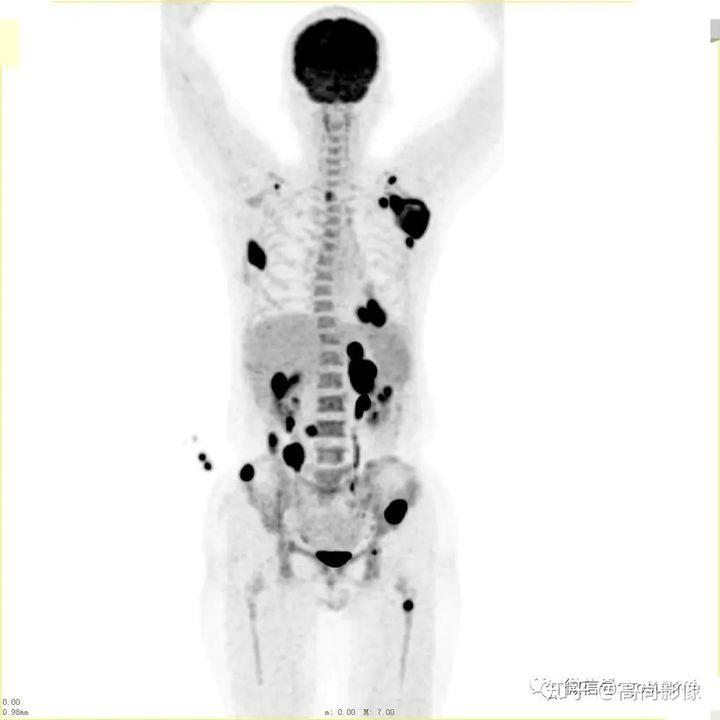

(右肺癌全身多發(fā)轉(zhuǎn)移)

方大爺?shù)腜ET/CT結(jié)果強烈提示肺癌伴全身多發(fā)轉(zhuǎn)移,已經(jīng)失去手術(shù)機(jī)會,但仍有繼續(xù)化療的機(jī)會。

肺癌化療前評估的MIP圖

(最大密度投影圖)

肺癌化療后評估的MIP圖

由此可見,惡性腫瘤化療前后的全身PET/CT評估有多重要,尤其對于惡性腫瘤患者來說,時間就是生命,早一天完善診斷,早一天得到正確的治療,預(yù)后就會更佳。